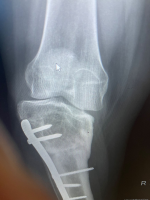

Mr Mughal is an experienced Consultant Orthopaedic Surgeon specialising in knee and hip surgery, with a particular focus on complex knee conditions and deformity correction. Born in Birmingham, he graduated in Medicine from Leeds University with Honours in Biochemistry and was awarded the prestigious William Macadam Prize in Medicine. He completed his surgical and specialist orthopaedic training in the West Midlands, followed by a dedicated Knee Fellowship in Derby, before being appointed as a Consultant at New Cross Hospital, Wolverhampton.

With more than 1,000 knee and hip replacements performed, Mr Mughal has extensive experience across all aspects of knee surgery. He has developed one of the largest specialist practices in the West Midlands for kneecap instability and has significant expertise in treating sports related knee injuries. His research includes publishing one of the world's largest series combining alignment and ligament surgery for recurrent kneecap dislocation, as well as widely adopted techniques for patellar realignment.

Mr Mughal is also highly experienced in deformity correction for both adolescents and adults, including knock knee, bow leg deformities and the complex condition known as miserable malalignment syndrome. He uses advanced computer based and 3D modelling techniques to plan personalised corrective surgery, aiming to preserve joints affected by early osteoarthritis. When combined with cartilage regeneration procedures, this approach enables him to offer a comprehensive and tailored treatment pathway.

Tibial osteotomy - (5-50)